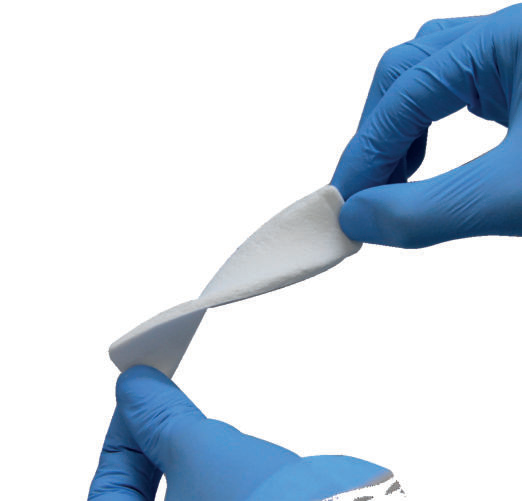

- Można je ciąć, składać i łatwo sklejać ze sobą.

- Nawilżony pasek Flexible Graft zwiększa swoją elastyczność.